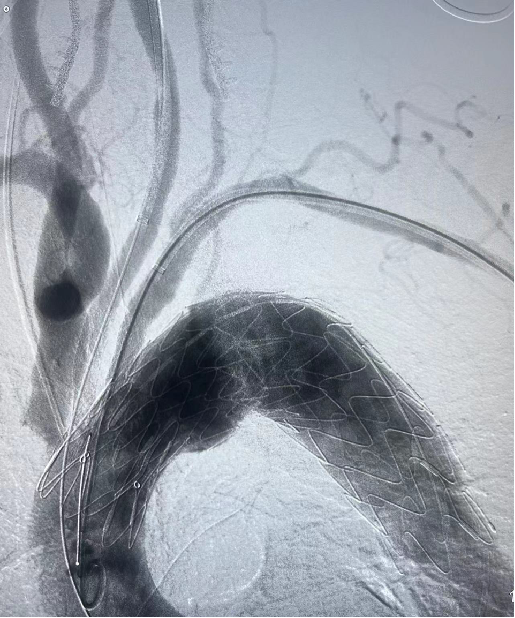

case 3

III型弓合并长段动脉瘤病变,LSA开口位于瘤体且与主动脉弓夹角小,病变累及长度长,手术截瘫风险高。

传统开窗技术因血管成角小、路径迂曲难以精准定位。

通过三开窗技术(LSA+LCCA+其他分支)完成重建,Futhrough系统的高顺应性和行程控制能力有效避免了血管损伤,术后截瘫风险显著降低。